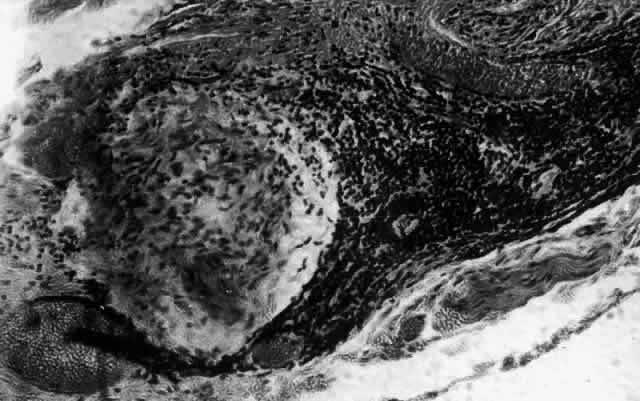

can be mistaken for malignant melanoma.  Fig. 19. Anterior necrotizing scleritis. The eye was removed because of loss of

vision and intractable pain. No form of steroid was given to this patient

because of a severe Pseudomonas infection of the chest. (Courtesy of Professor N. Ashton) Fig. 19. Anterior necrotizing scleritis. The eye was removed because of loss of

vision and intractable pain. No form of steroid was given to this patient

because of a severe Pseudomonas infection of the chest. (Courtesy of Professor N. Ashton)

What is clinically represented solely by inflammation and edema is histopathologically

a granulomatous lesion of the sclera, the center of which

consists largely of plasma cells, lymphocytes, and mast cells (Figs. 21 through 23). Foster and colleagues have identified the cellular subsets and glycoproteins